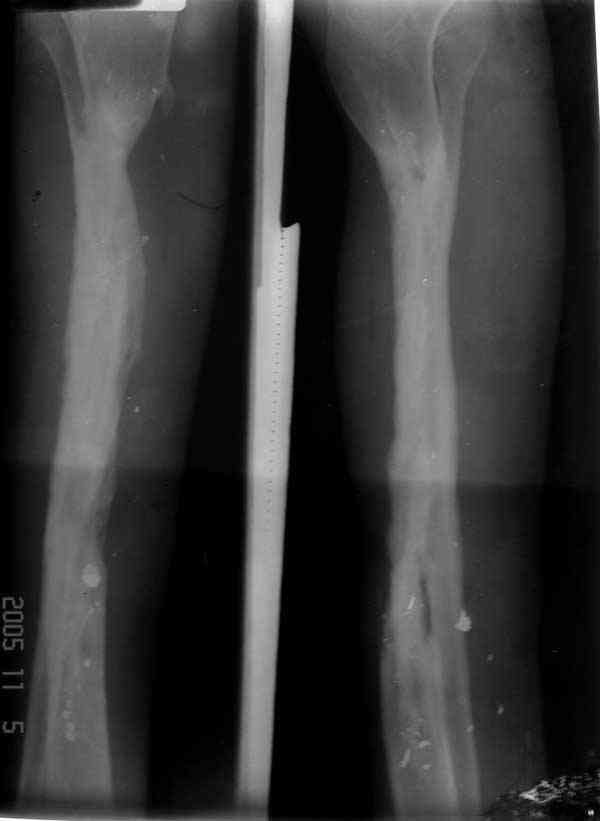

Re: Дефект большеберцовой кости - что делать? Ваше

У нас не задумываясь провели бы vascularized fibular graft.

Можно было split fibula transfer, но для этого

необходима интактная малоберцовая.

Предложенный Александром вариант, кейдж плюс стержень - неплохая идея, уменьшает срок восстановления, и без наружных атрибутов фиксатора.

Хотя для уменьшения размера дефекта (кейдж) можно было предложить предварительную однофокальное удлинение в проксимальном метафизе, потом применение стержня.

Стержень можно забить через голеностоп в таран, тогда удлинится и усилится короткий дистальный конец.

Если смелость больной достаточна для аппаратного лечения, тогда другой вариант, комбинация удлинения в проксимальном отделе большеберцовой и утолщения малоберцовой в нижней трети, где диаметр малоберцовой позволяет.

Для сокращения времени малоберцовую можно расширить быстрыми темпами, а в образовавшуюся щель ввести костный графт.